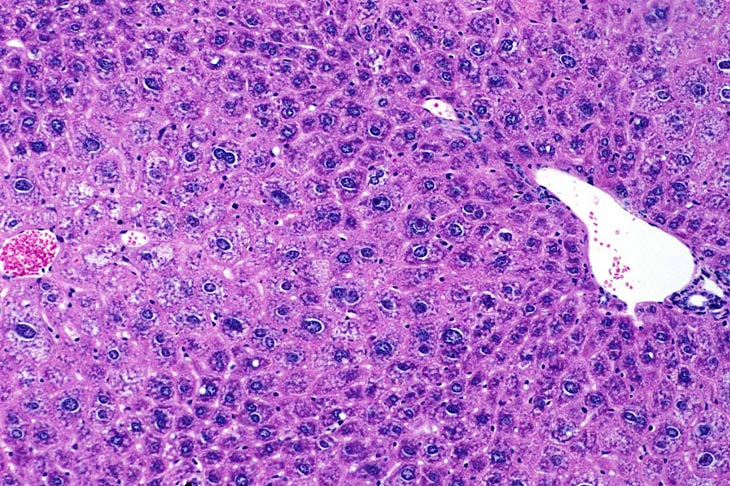

Centrilobular hepatocytomegaly (hypertrophy) in a mouse given phenobarbital for 8 months. Note the prominent eosinophilic cytoplasm reflective of smooth endoplasmic reticulum proliferation.